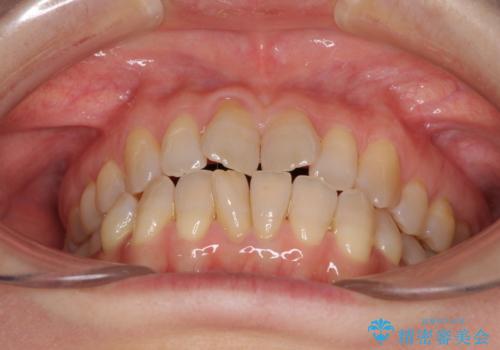

前歯の叢生と切端咬合 インビザラインによる矯正治療

- 前歯のデコボコを気にして来院された患者様です。

上下前歯の先端同士が接触する切端咬合であったため、上顎は歯列を拡大し、下顎はIPR(歯と歯の間を削る)により叢生を解消しながら歯列を小さくすることとしました。

治療前から歯肉退縮が認められ、矯正治療により悪化する可能性が考えられたため、無理のない歯の移動と頻繁な経過観察を行いました。